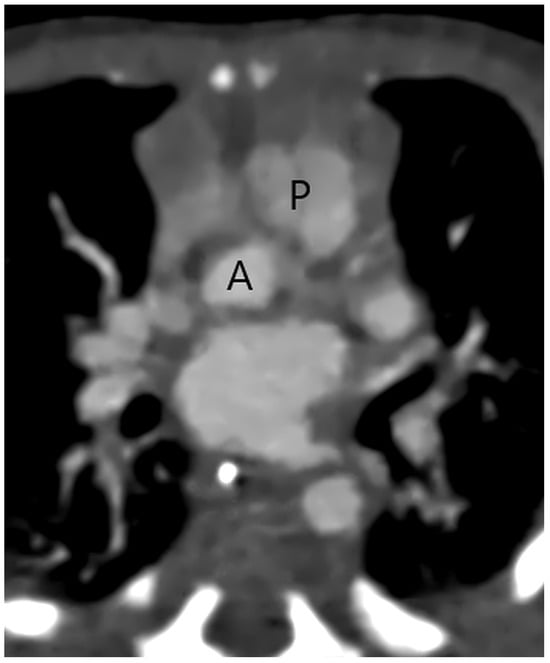

Figure 1.

A separate aortic (A) and pulmonary (P) valve in a patient with a type 2 aortopulmonary septal defect at CT angiography.